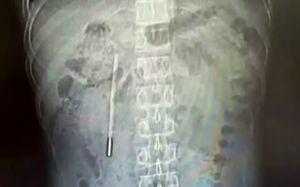

[워싱턴=AP/뉴시스]도널드 트럼프 미국 대통령이 지난 13일(현지 시간) 백악관 집무실 밖에서 취재진 질문에 답하고 있다. 2026.04.14.